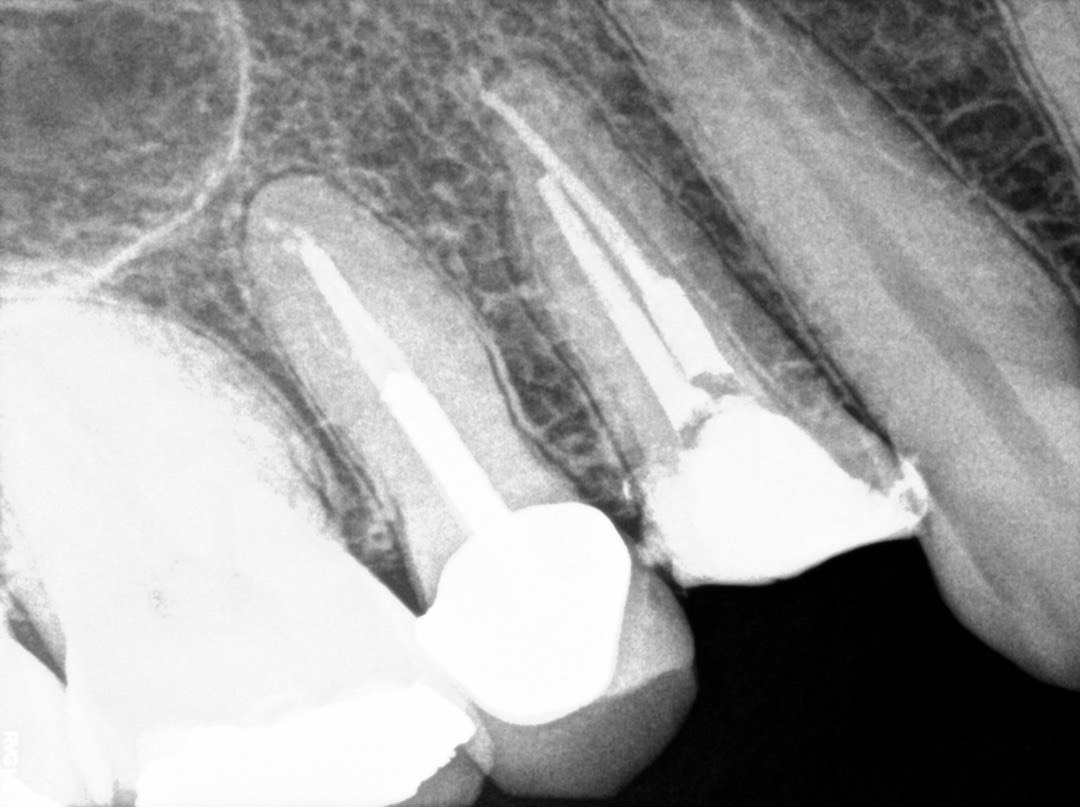

1. Evaluate the root canal treatment of tooth # 2.5?

2. What option cannot be selected for root canal treatment of tooth # 2.6?